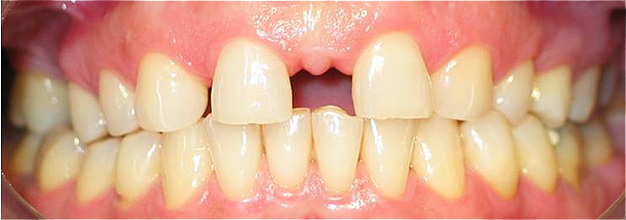

Apinhamento dentário com os dentes caninos em desoclusão (classe II, divisão 2).

![]() |